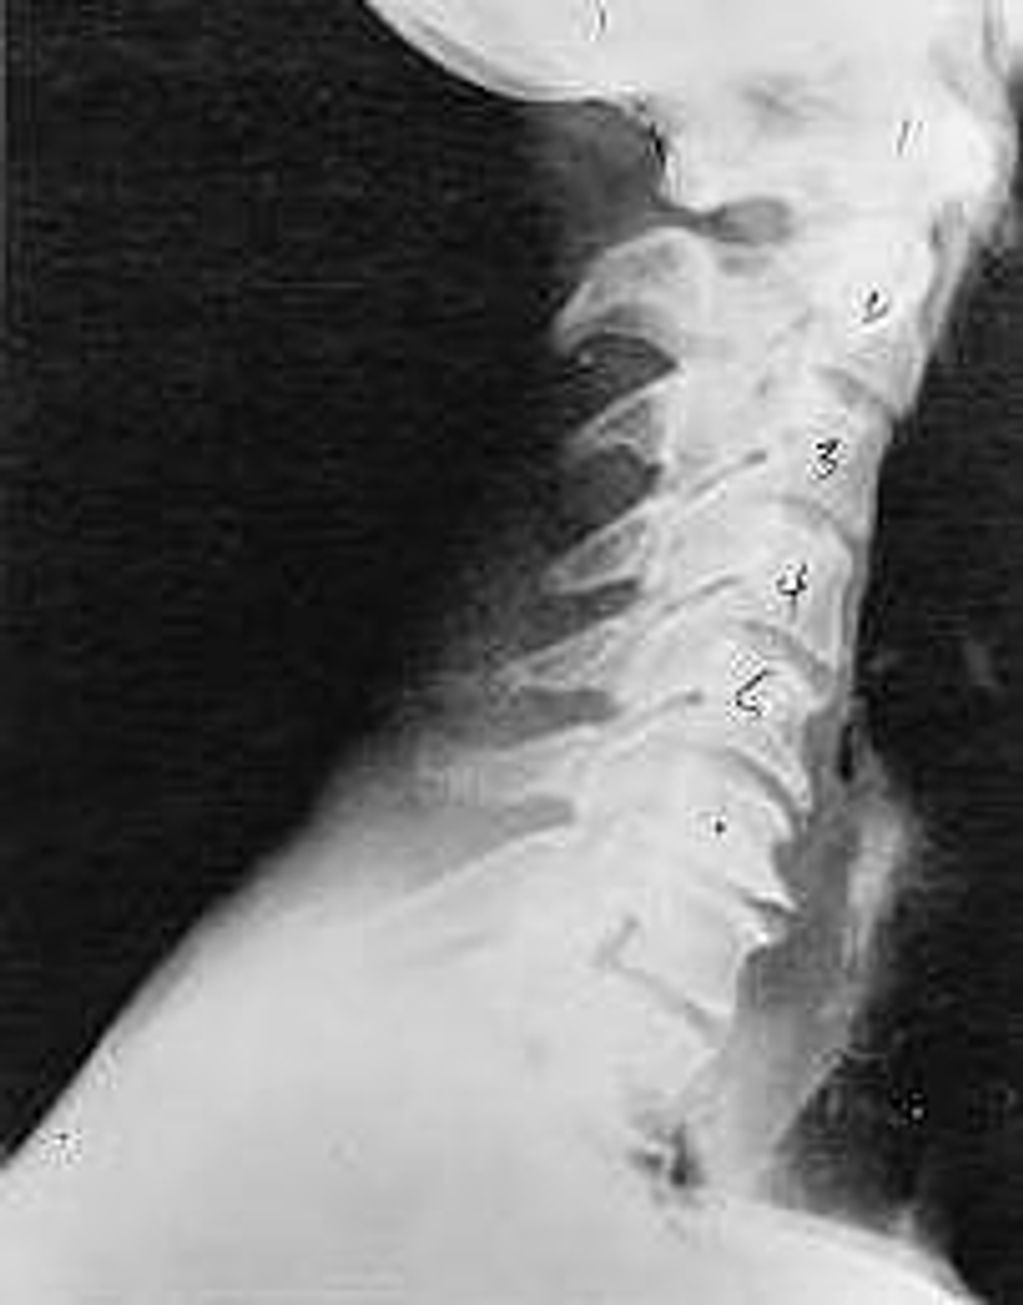

Near Normal

This is a side x-ray view of the neck. As with all the pictures you will see on this page, the patient is looking to the right of the screen, so you are viewing the right side of their neck. We will call this picture a "near normal" spine. Compare this spine with the ones you will see below on this page. Notice the normal forward curve of the neck. This curve helps absorb shock. Not